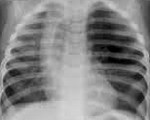

В качестве первичного скрининг-обследования всем пациентам проводится рентгенография легких. При этом на снимках обнаруживается повышенная воздушность пораженной доли, смещение средостения в здоровую сторону, уплощение купола диафрагмы. Расширенное обследование направлено на оценку тяжести анатомо-функциональных изменений в легких и выбор тактики лечения.